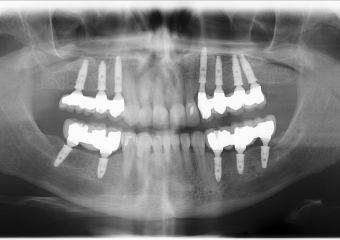

Rx Final - levantamento de seio bilateral - implantes